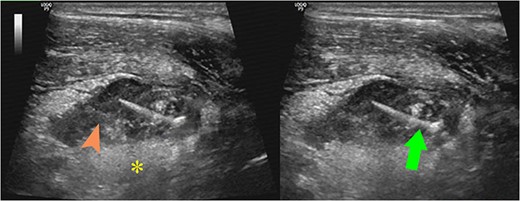

A 43-year-old man was hospitalized with dull pain in the right lower quadrant of the abdomen for 3 days. Accompanying symptoms were low-grade fever and nausea. In the emergency department, vital signs showed blood pressure 130/80 mmHg, heart rate 80 beats per minute, body temperature 37.9°C, and respiratory rate 22 per minute. Clinical examination revealed localized rebound tenderness on palpation at the right lower abdominal quadrant. Laboratory findings showed elevated white cell count of 15 000/mL (normal value <11 000/mL). Abdominal ultrasonography showed a large pus-filled appendix with an internal thin echogenic structure extending outward from the muscle layer and fatty infiltrates in the right iliac fossa (Fig. 1). In the ultrasound room, after being explained by the sonographer about the suspicion of appendicitis due to foreign bodies, the patient remembered and reported that he ate fish 5 days ago. CT scan performed then confirmed perforated appendicitis caused by a foreign body (Fig. 2). The patient underwent laparoscopic appendectomy without complications. The postoperative diagnosis was perforated appendicitis caused by fishbone (Fig. 3). The patient recovered and was discharged within 4 days.

Ultrasound images showed a large pus-filled (arrowhead) appendix with a thin internal echogenic structure (arrow) extending outward from the muscle layer with surrounding fat infiltration (asterisk).